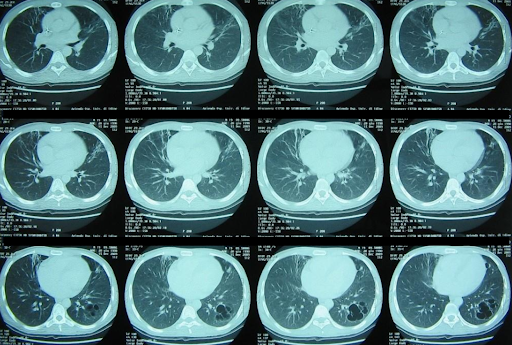

Eine Röntgenaufnahme des Brustkorbs zeigt ausgedehnte beidseitige Lungenverschattungen, die auf der rechten Seite stärker ausgeprägt sind, mit einem gemischten parenchymalen und pleuralen Muster. Vor dem Hintergrund von Fieber, Atemwegsbeschwerden und radiologischen Befunden wird die Diagnose einer schweren ambulant erworbenen Lungenentzündung gestellt. Es wird mit der intravenösen Gabe von Levofloxacin begonnen und über eine Venturi-Maske wird zusätzlicher Sauerstoff verabreicht.

ARDS_1.png

Die bei der Vorstellung durchgeführte Röntgenaufnahme des Brustkorbs zeigte beidseitige Lungeninfiltrate, die zunächst mit einer schweren ambulant erworbenen Lungenentzündung vereinbar waren.1